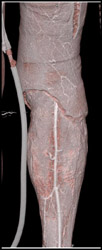

Diagnosis

Normal CTA